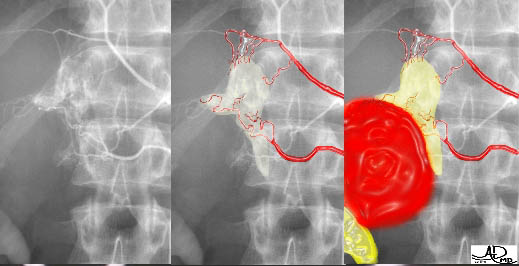

Venous Drainage – Venography |

This series of three images reflects a study called “adrenal vein sampling” which requires the simultaneous catheterization of the adrenal veins. This procedure is used to identify relative and absolute concentrations of hormone secretion from the glands to distinguish between normal, bilateral hyperplasia, and unilateral adenoma.

|

The first image shows the catheters in each of the adrenal veins. The second image is a venogram of the right adrenal vein, and the third a venogram of the left. The venogram is mainly performed to confirm that the catheter is in the correct position, because the veins, particularly the right, may be difficult to find and other small veins coming into the IVC may masquerade as adrenal veins. It is absolutely essential to be in the “right place at the right time” for this test. Courtesy of: Ashley Davidoff, M.D. |

This image is an overlay and an enlarged version of the first image above. It shows the right catheter entering the short right adrenal vein, exiting from above the right gland, and entering the IVC. The left adrenal vein, which is longer, exits from below the left gland and enters into the left renal vein. The insert of the “duel” is a reminder of the short vein on the right and the long vein on the left. Courtesy of: Ashley Davidoff, M.D. |

This image is an overlay and an enlarged version of the second image from the initial series above. It shows the right catheter entering the shorter right adrenal vein, exiting from above the right gland, and entering the IVC. The yellow overlay is an approximation of the right adrenal gland. Courtesy of: Ashley Davidoff, M.D. |